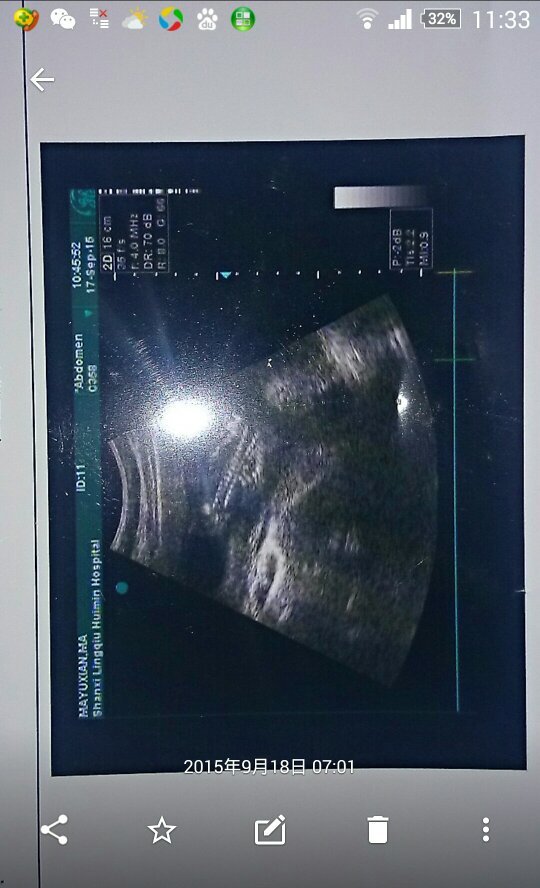

可以看出男孩女孩吗?呵呵

亲,从超声波的检查图是看不出胎儿的安剩性别的,只有当时的检查神指医生才能看出胎儿的性别(怀孕四个月以上),所以从这张图上看出结果的都是骗你的。不要相局筛录信。

连个人形都看不到,还分男女,你看的不会是前裂腺吧!